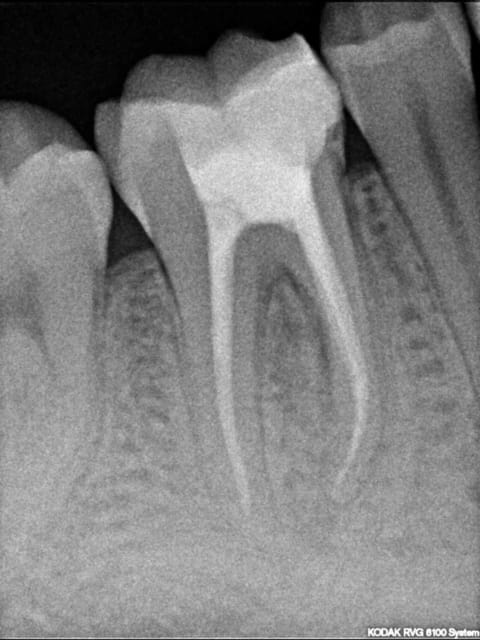

4 mois post-op du cas posté sur la page précédente.

félicitations, beau boulot.